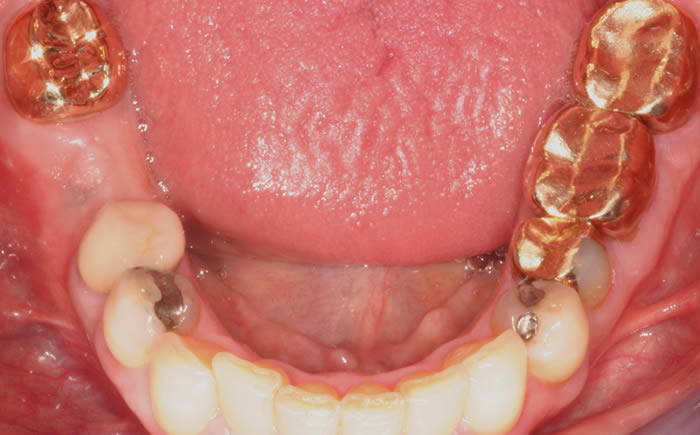

More back teeth replaced by dental implants

Case Three (2 images)

Case Four (4 images)

Case Five (4 images)

Case Six (8 images)

Case Seven (4 images)